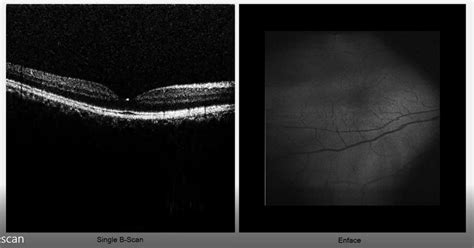

OCT Interpretation: A specialist's guide to optimizing the most ...

zeiss.com